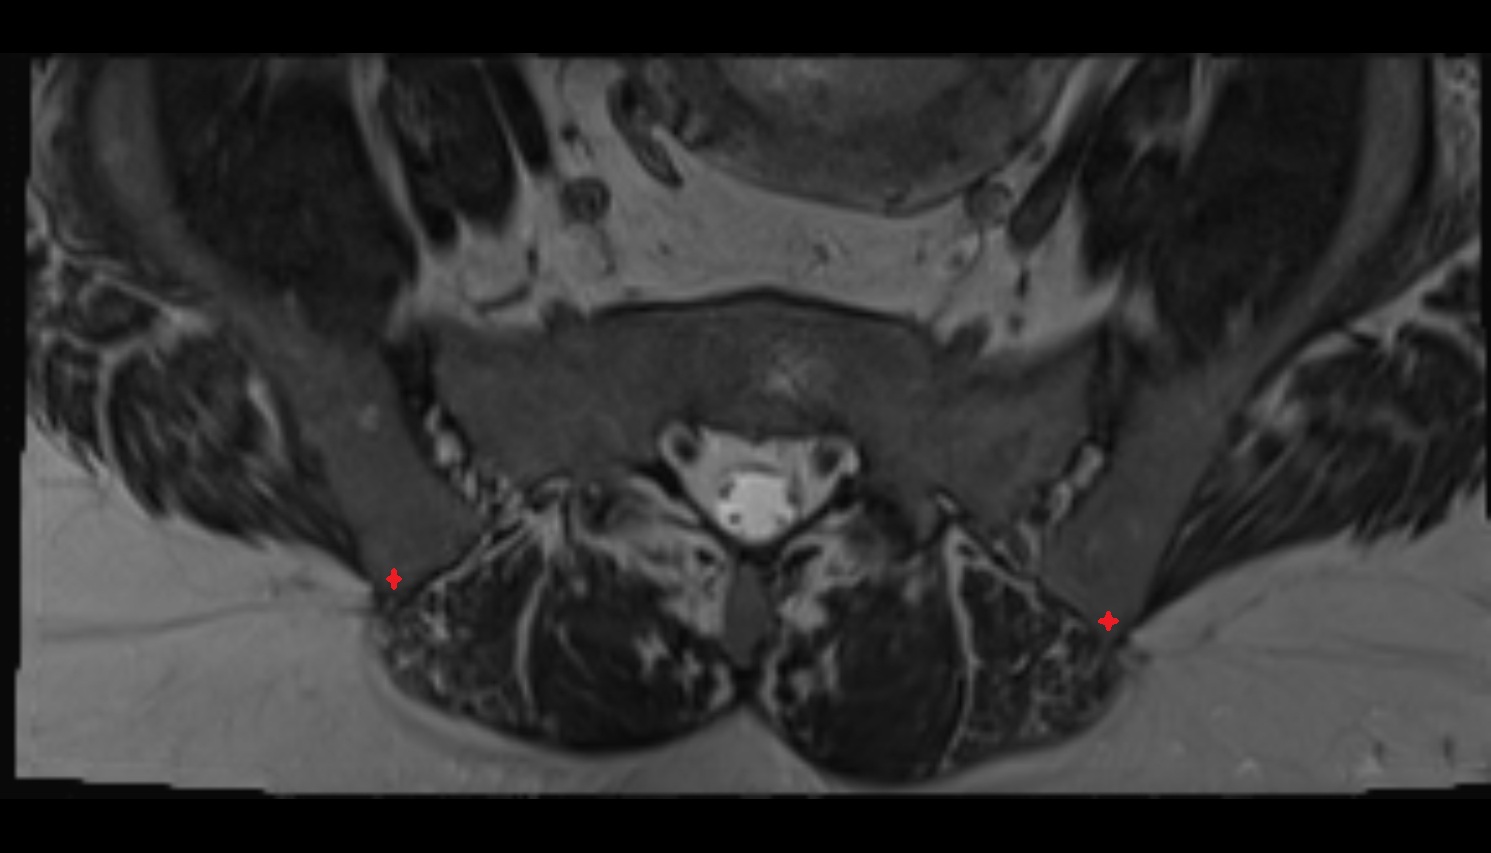

- Sacroiliac joint